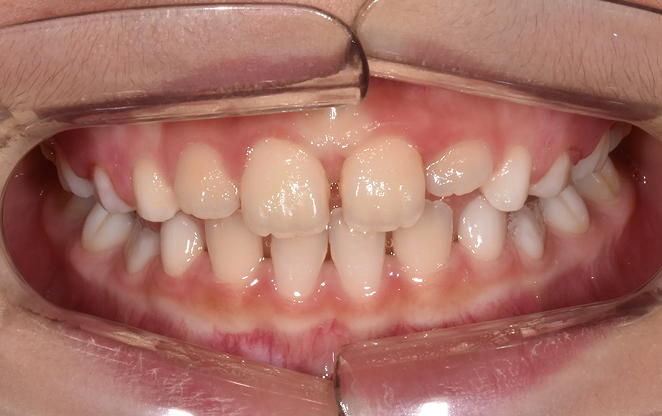

발치 없이, 턱과 얼굴의

조화를 만들어가는 비발치교정

어려운 결정을 내리지 않고도 아름다운 미소를

찾아갈 수 있는 길이 있습니다. 비발치 교정은 발치를 하지 않고

치아를 이동시켜 공간을 확보하는 방법입니다.

치아의 배열을 세심하게 조정해 공간을 확보하고,

치아가 자연스럽게 자리할 수 있도록 합니다.